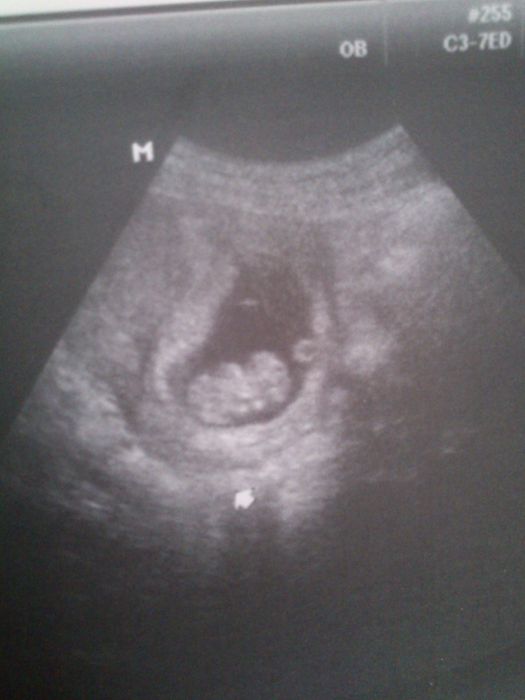

Jinak srdíčko nám tluče :-) už je to takovej buřtík. Dostala jsem už průkazku. A holky...tohle je UZ dělanej přez břicho :-) mazec

Ahoj Peti, fotečka moc hezká, takže ultrazvuk se už dělá přes břicho?